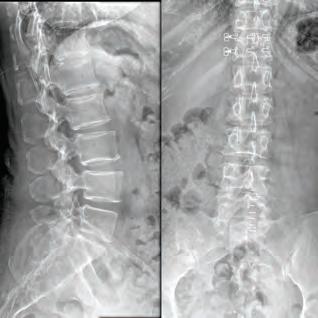

Texas Back Institute (TBI) has served the North Texas area in spine care for over 45 years. An uncompromising desire to put patients first and provide individualized spine care has helped change the treatment options available to patients for neck and back pain.

Today, TBI is a leader in artificial disc replacement, minimally invasive spine surgery, complex revision surgery, and treatment of spinal deformity. TBI has trained hundreds of surgeons, scientists,

and allied health professionals now practicing worldwide. Its research institute employs state-of-the-art technology and is actively involved in many clinical trials, including artificial disc replacement, minimally invasive technologies, and robotic spine surgery. Texas Back Institute has remained one of the most academic practices in spine care. It is one of the largest multidisciplinary spine centers in the world, providing comprehensive care for neck and back pain. With a fully dedicated staff of board-certified orthopedic spine surgeons, neurosurgeons, physiatrists, and physical therapists, the TBI team works together to support its mission of helping patients get back to life. The 26 physicians at Texas Back Institute are leaders in the surgical and nonsurgical treatment options for back and neck pain, from the most common outpatient procedures to the most complex cases. Thanks to the unmatched expertise of the medical staff, the advanced diagnostic testing, and an unparalleled commitment to patient care, the Texas Back Institute physicians can identify the potential cause of your pain and create a treatment plan specific to your needs.

Texas Back Institute has developed several spine specialty programs. These include the Minimally Invasive Spine Surgery Center, Center for Disc Replacement, Scoliosis and Spine Tumor Center, and Complex Back Surgery Center. These programs give patients access to highlytrained care teams who focus specifically on these areas of spine care, allowing patients in the North Texas area access to treatment options for their individual problems from physicians with extensive experience in these areas.

“At Texas Back Institute, finding the right solution for each patient and offering the least invasive treatment is core to our belief and the foundation for all treatment plans.” Dr. Michael Duffy.